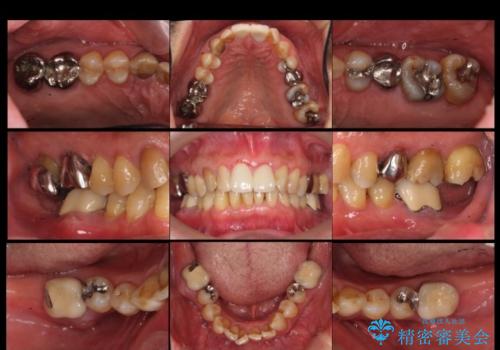

奥歯が割れてしまった インプラントでかめるように 全体的な治療も

- 右下の奥歯が割れてしまい、抜歯を行いました。

ブリッジにできない位置であったため、インプラントでかめるようにしました。

また、向かい合う上の歯が挺出(伸び出してしまうこと)しており、インプラントを入れることが難しかったため、長さを短くかぶせ治しました。

また、上顎前歯以外の根の治療のやり直しを行いました。

上顎前歯は他院で根管治療とセラミックを行なったとのことで、歯肉縁下形成のため、歯肉の腫れが治りにくい状況でしたがやり直しは希望されませんでした。

左下に関しては、経過観察を行い、歯が割れたりした場合にインプラントを考えることになりました。